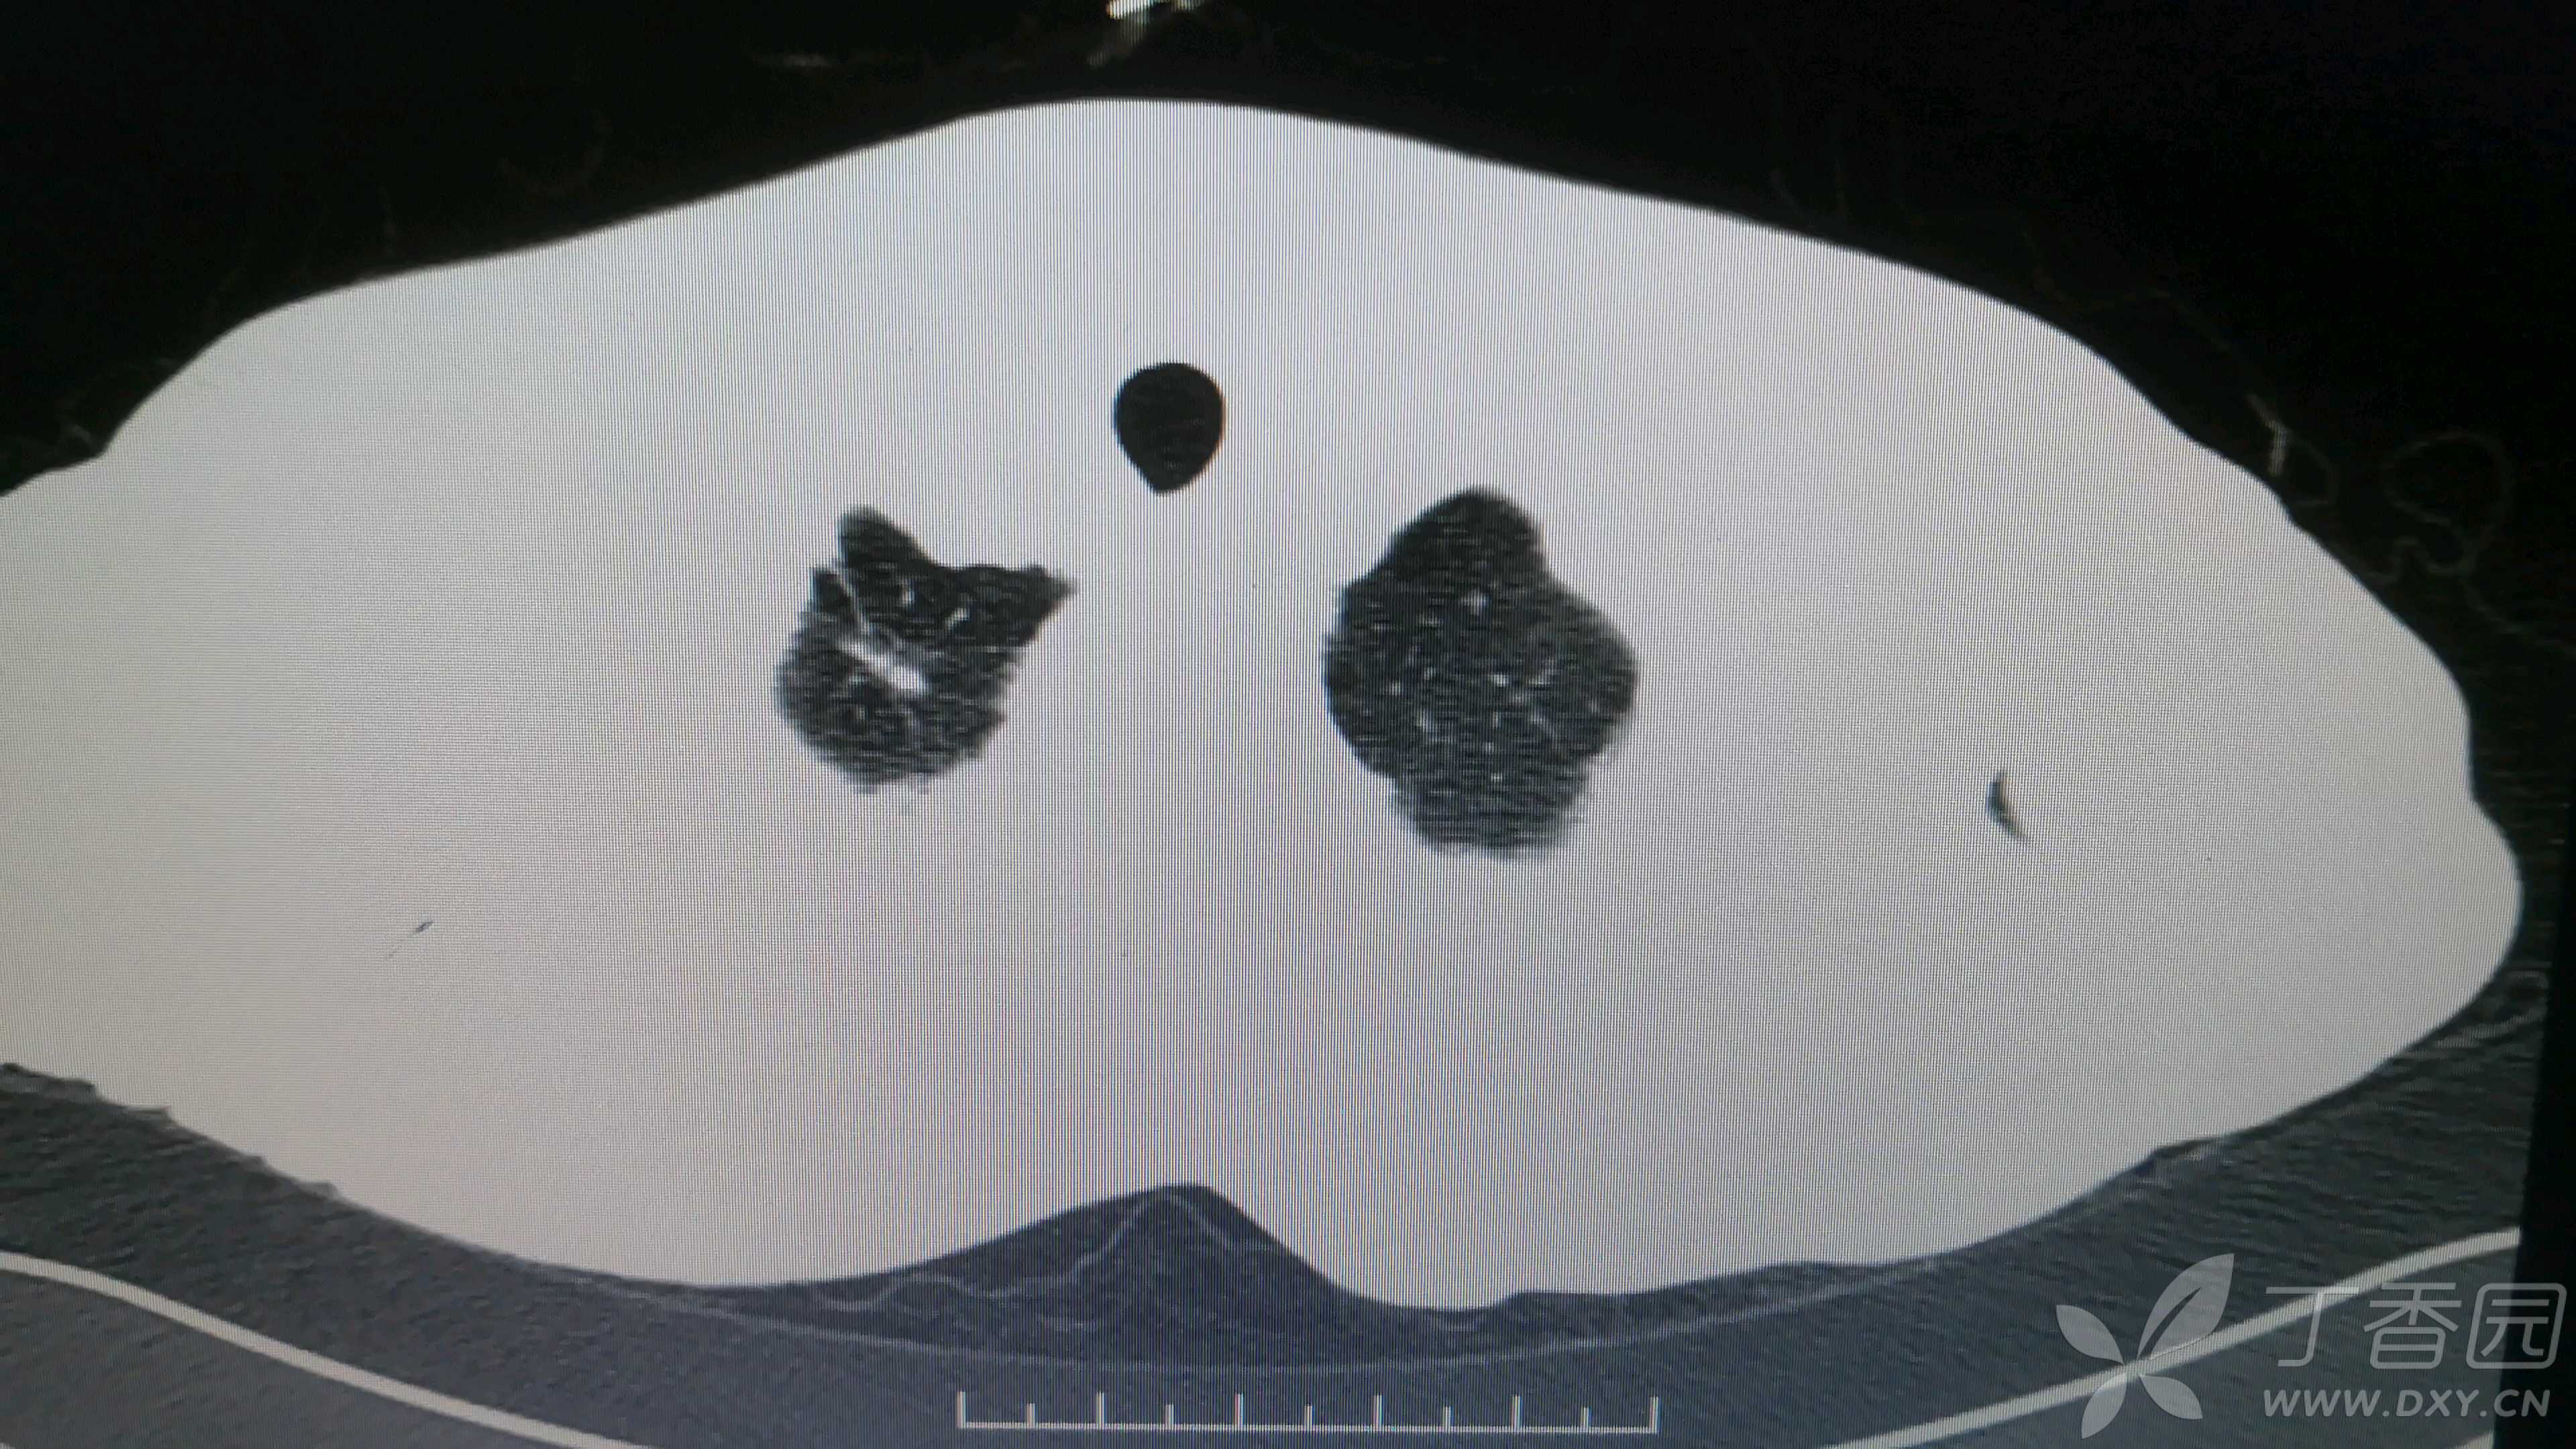

简要病史:反复咳嗽、咳脓痰40余年,气喘10年,加剧2周。

体格检查:SpO2:72%,双中下肺闻及中小湿啰音。

辅助检查:见图

临床诊断:支气管扩张并感染